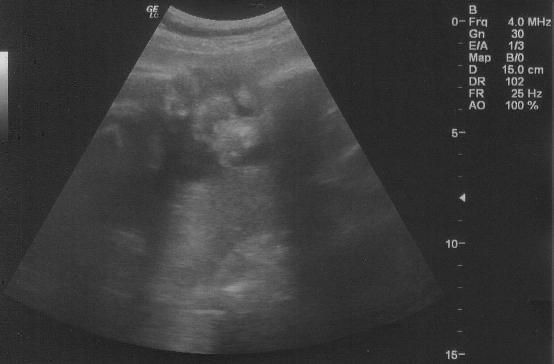

Tegnap megnézett minket doki, minden rendben van Benivel... Nagyon szép baba arca van!!! :D Sajna ezt a kép nem adja vissza amit feltöltök nektek... Már 1 600 gramm kb... Fejlődik szépen. Az adatait külön képen láthatjátok.

Kép Adatok

Kép Ez a fejecskéje lenne...

Kép Ez pedig a kukac, pontosabban a mogyorócskák :D